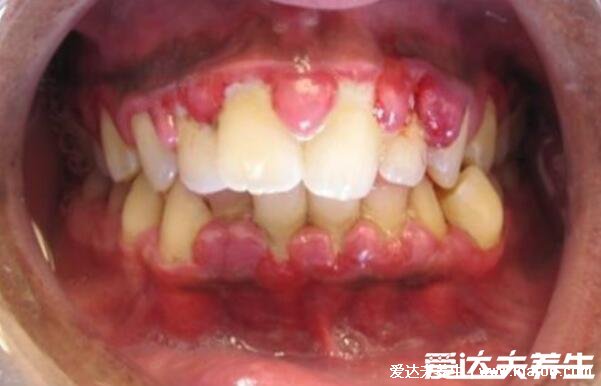

牙龈癌的早期三大症状

2、乳头状和结节状肿物

在口腔内长菜花样、乳头状和结节状的肿物也是牙龈癌的早期症状之一,比较容易出血,无法正常的咀嚼食物以,就连张口都会受到阻碍。